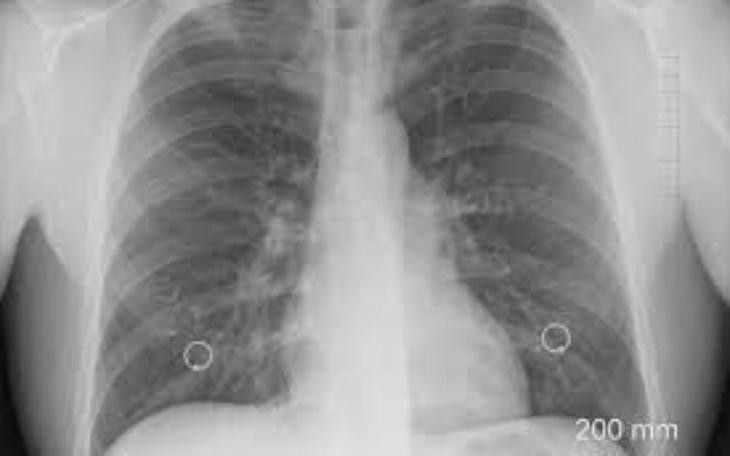

Witam kochani!!Trafiłam do szpitala z podejrzeniem zaplenia płuc, po 2 antybiotykach kaszel nie mijał.Po zrobieniu zdjecia dokładnyc badań lekarze skierowali mnie na biopsje bo wyniki były bardzo złe.Wykryto u mnie raka płuc diagnoza mnie załamała.Bo ten rak to wyrok.nowotwor płuc umieszczony w opłucnej i jest nie operacyjny ale walka cały czas trwa.Po chemi było troche lepiej gdy juz sie zmniejszył.Choc chemia przestała działac. Rak sie rozrasta i zaatakował moj kregosłup.czeka mnie teraz radioterapia.Jesli jestes mi w stanie pomoc w walce z gory DZIEKUJE za pomoc,kazda wpłata jest dla nie cenna